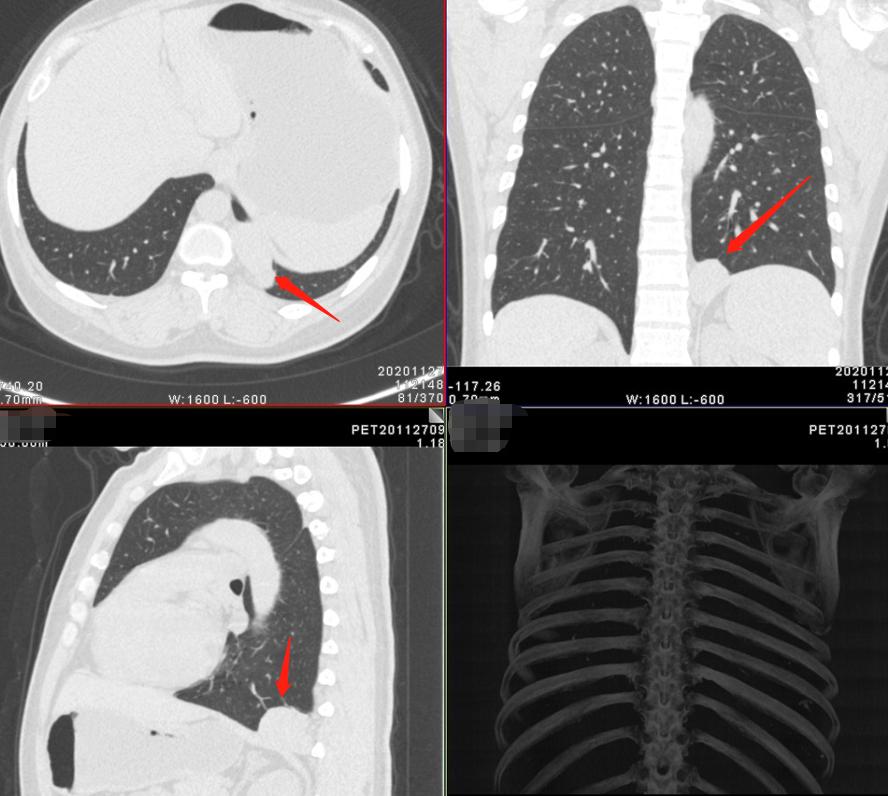

2.女性 56岁 体检发现右肺上叶前段占位,无特殊不适。

啥也不说了,实性软组织结节,大小约1.9cm×1.5cm,和病例1一样,该有的征象都有了……而且还出现支气管的截断、鼠尾征这些典型的特点。但是有没有不太符合的,我们在诊断的时候还是留了一手,建议活检除外感染性病变。

病理提示隐球菌感染